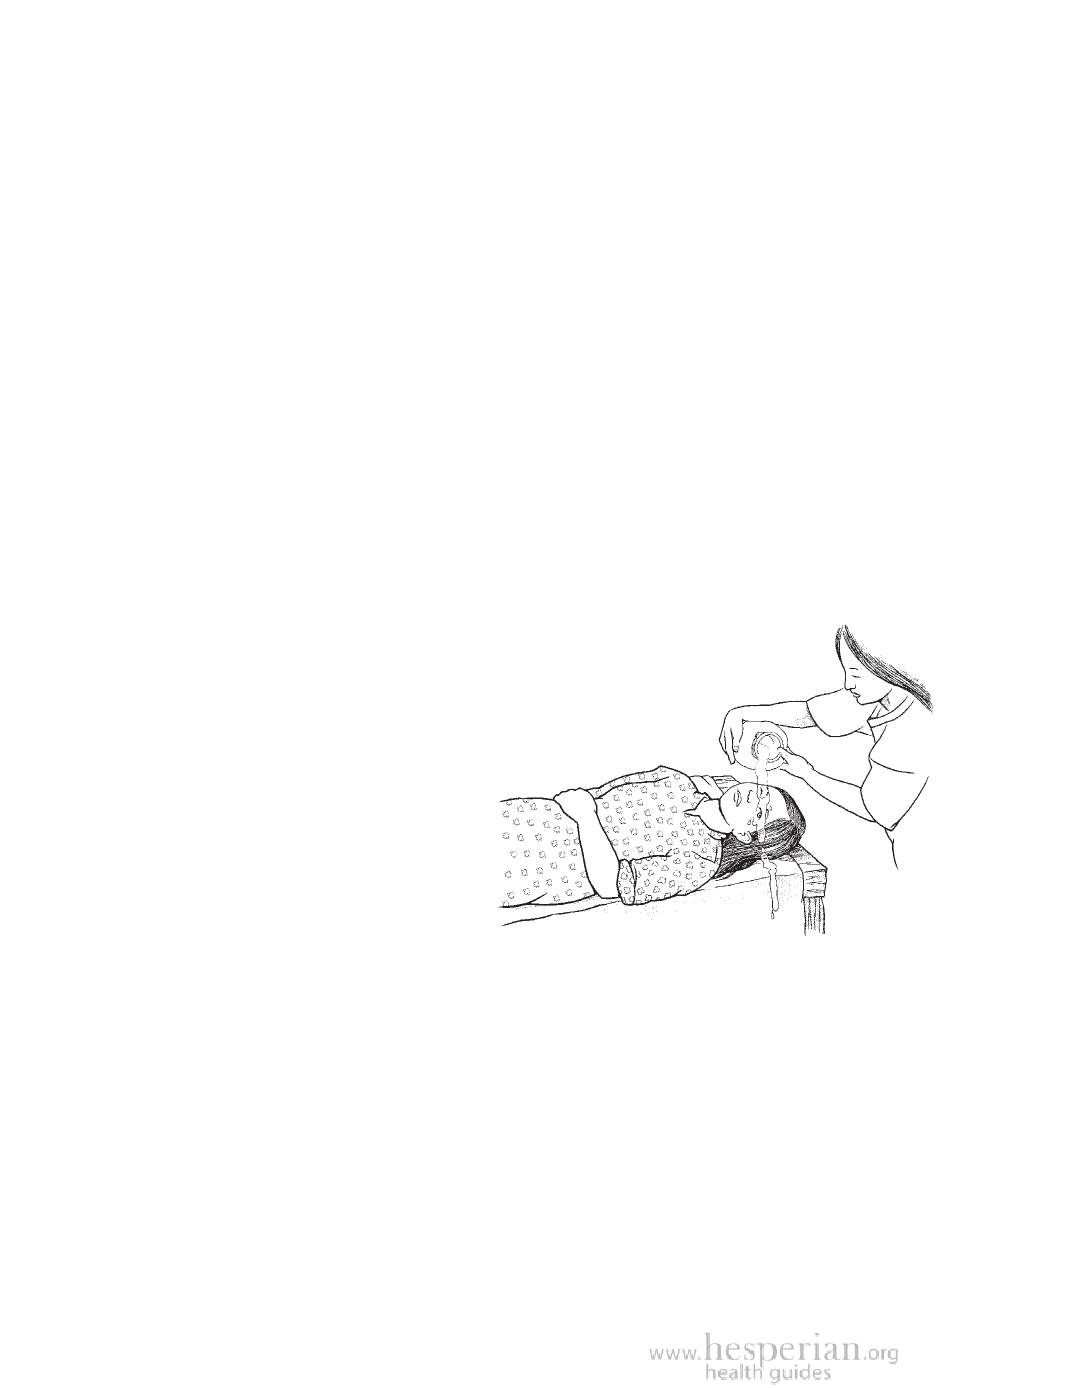

• If chemicals got into the eyes, rinse with clean

water for 15 minutes. Pull the eyelid away and

move the eyeball in a circle so the

entire eye is washed.